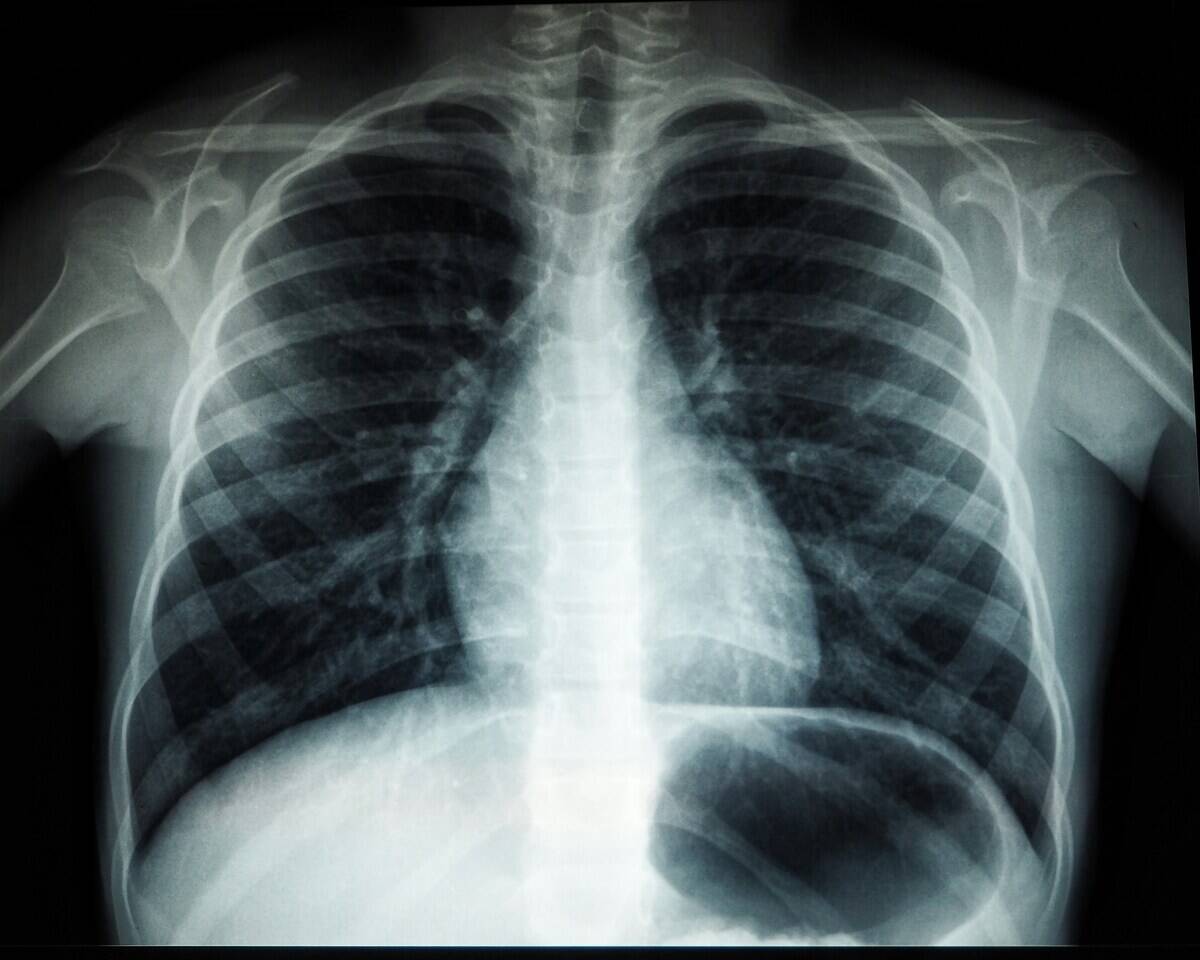

“Nothing will get passed around an Emergency Room faster than the x-ray of the foreign object”

One Redditor pointed out in a short and succinct post that while the people working in emergency rooms are professional and will help you with your issue, they’re not above a little gossip.

This means that if you ever get something weird stuck in a weird part of your body, you’d better believe that staff in the ER will talk about it, and probably check out your x-ray. “Truth and being nice goes very far in the ER,” they conclude. “We’ve seen it all. Just tell us the truth.”